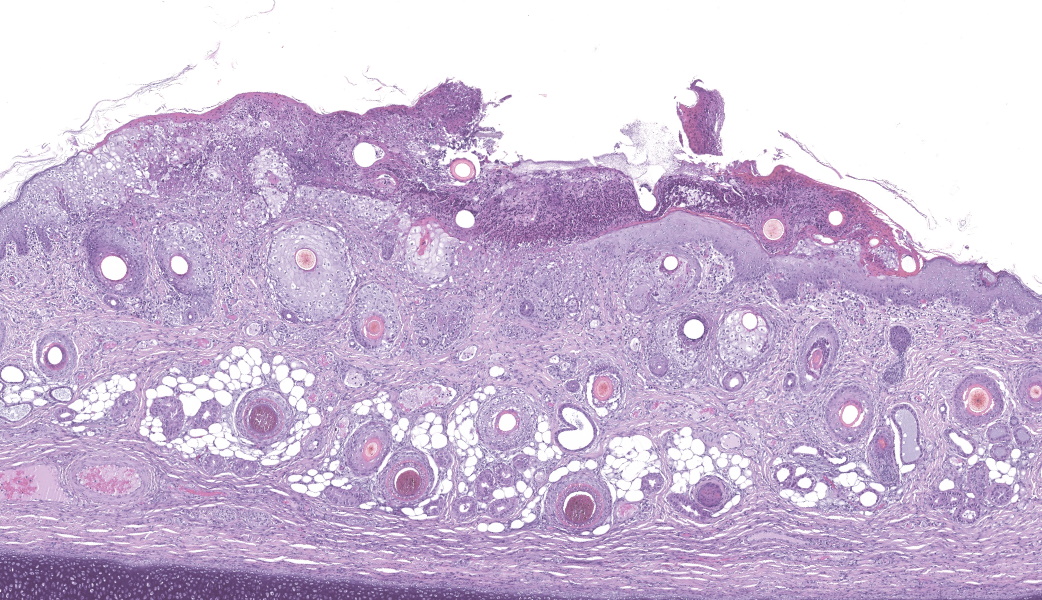

Haired skin (ear, prepuce, and inguinal area): affecting 20% of the evaluated section there is a proliferative and necrotizing process that mainly affects the epidermis. The epidermis and hair follicle epithelium show the following features: stratum corneum with diffuse mild compact hyperkeratotic orthokeratosis with multifocally serocellular crusts composed by cellular debris, degenerated keratin, degenerated neutrophils, and multiple superficial coccoid bacterial colonies (secondary contamination). Also, stratum spinosum shows multifocal marked thickening (acanthosis), and numerous keratinocytes display ballooning degeneration and intracytoplasmic perinuclear 2-5 ?m eosinophilic inclusion bodies. Multifocally, in the most affected areas, there is marked neutrophilic exocytosis, and numerous keratinocytes lost intercellular connections and undergo lytic necrosis. Superficial and mid dermis show perivascular to diffuse, moderate to severe inflammatory infiltrates composed by viable and degenerated neutrophils, macrophages, and lesser numbers of lymphocytes and plasma cells. Significant lesions were not seen in the hypodermis.Contributor's Morphologic Diagnoses:

Morphologic diagnosis: Haired skin; severe, subacute, proliferative, necrotizing, and crusting dermatitis with intracytoplasmic eosinophilic inclusion bodies. Etiologic diagnosis: Poxviral dermatitis. Etiology: Swine poxvirus.Contributor's Comment:

The typical histological features of SwPV infection comprises hydropic degeneration of keratinocytes of the epidermal stratum spinosum and follicular epithelium during the papular phase. As a result, thickening of the epidermis due to mild spongiosis can be observed; however, epidermal hyperplasia caused by SwPV is usually less prominent than that caused by the other poxviruses.7 Other finding are eosinophilic inclusion bodies in the cytoplasm of infected cells.7 Regarding inflammation, the damage caused by virus replication on keratinocytes causes recruitment of neutrophils, eosinophils, lymphocytes and histiocytes, forming intraepithelial pustules, as well as in the superficial and mid-dermis.4,6,7

Haired skin: Dermatitis, necrotizing and proliferative, subacute, multifocal, severe, with ballooning degeneration and intracytoplasmic viral inclusions.